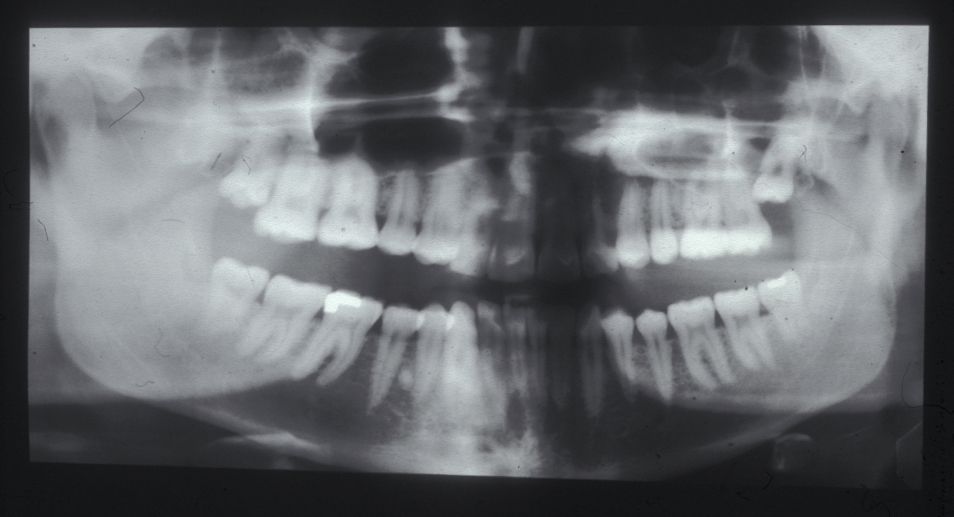

A panoramic radiograph, OPG, (orthopantogram; also referred to as a dental panoramic tomogram (DPT) reveals caries and periodontal disease, unerupted or impacted teeth, and the presence of coincidental pathology, such as cysts (see Figure 8 for an example).

Figure 8: Panoramic radiograph of a patient showing wisdom teeth destined for removal in an otherwise ‘dentally fit’ person.